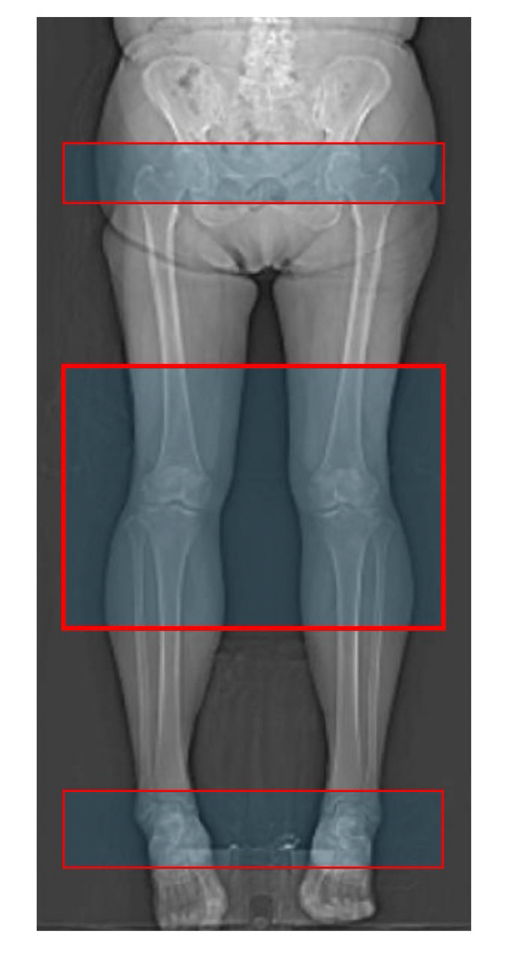

Computed tomography now plays a central role in three dimensional planning for joint replacement. It underpins implant sizing, version assessment, alignment analysis and the growing use of robotic and navigated workflows. While the value of CT based planning is widely accepted, far less attention has been paid to how these scans are acquired.

The anatomical and imaging requirements for arthroplasty planning are consistent, regardless of implant brand. Recognising this, harmonised, vendor-neutral CT protocols can replace fragmented, incomplete guidance. Procedure-specific protocols that clearly define scan coverage and acquisition parameters remove ambiguity, support radiographers, and enable reliable low-dose imaging that is fit for purpose. Standardisation does not mean a single one-size-fits-all scan, but a coherent framework grounded in clinical need rather than commercial convention.